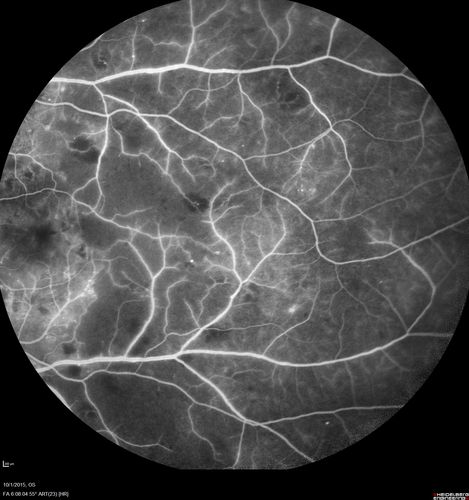

Hairy Cell Leukemia - Retinal Hemorrhage and twig Branch Vein Occlusion

79 year old man He has had hairy cell leukemia since 2002.  He is in remission.  His last blood tests were 9/2018.  He just moved down here and needs a new leukemia doctor.  His vision is fine.

VA OD: Dcc20/25

VA OS: Dcc20/25

IOP: TP: OD:12 OS:12